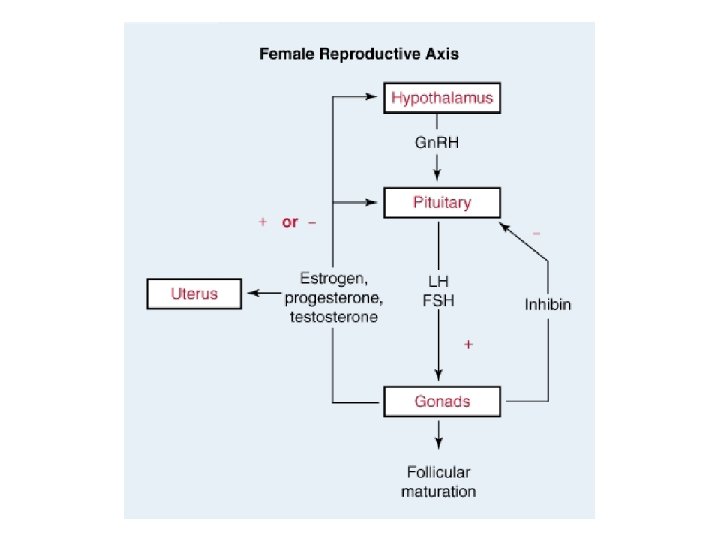

Gonadotropin Releasing Hormone (Gn. RH) • • Secreted by hypothalamus Pulsatile secretion is critical for activity Gn. RH secretion inhibited by estrogen Low levels of estrogen cause hypothalamus to release Gn. RH

Follicle-stimulating Hormone (FSH ) • • FSH hormone is secreted by anterior pituitary Turned on by Gn. RH Negative feedback inhibition with estrogen Causes maturation of dominant ovarian follicle

Luteinizing Hormone (LH) • • Secreted by anterior pituitary Turned on by estrogen Maintains corpus luteum Causes corpus luteum to secrete progesterone